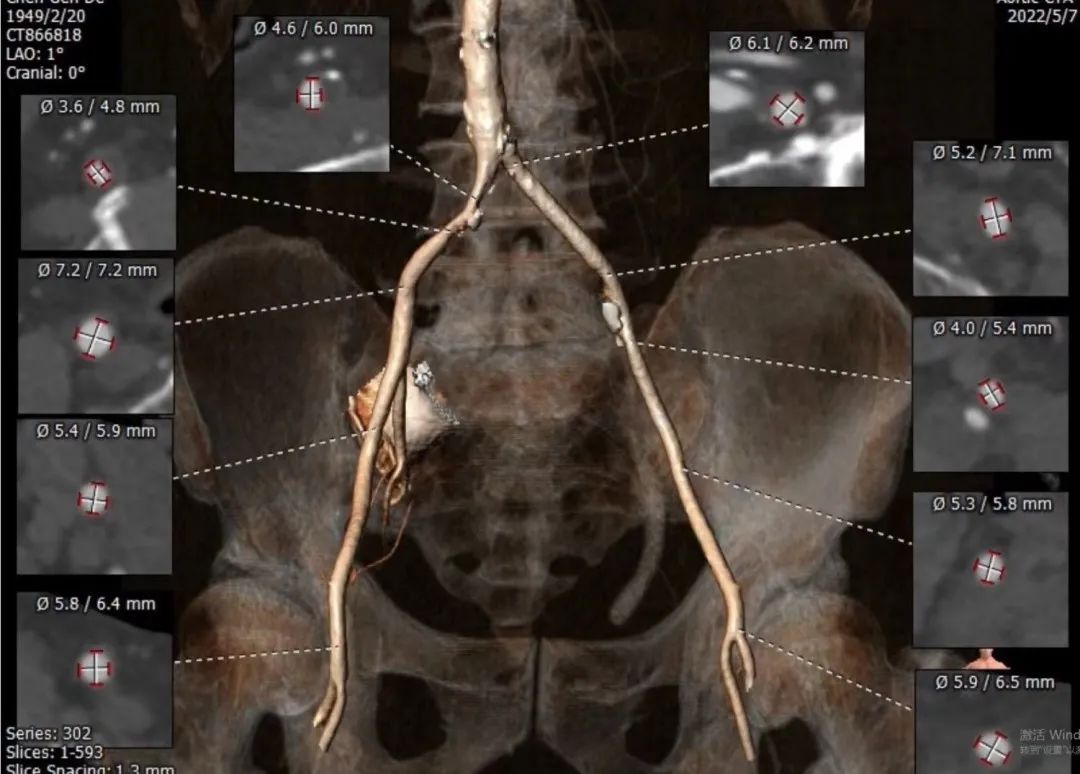

入路血管左侧分叉高,无迂曲。左侧血管平均最小内径4.7mm,右侧血管平均最小内径4.2mm